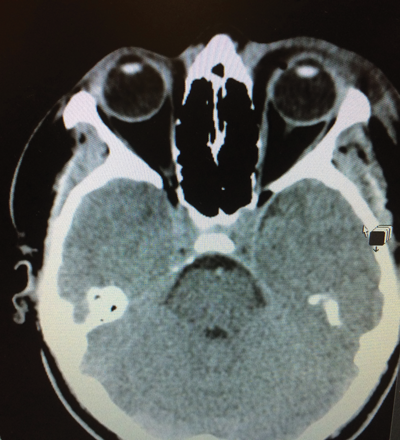

He was not (anymore?) under the influence of alcohol when he arrived at the hospital but still agitated, probably because of the fight that led to his injury. He presented with left upper and lower lid haematoma with some blood surrounding the lids and periorbital soft tissue swelling. He seemed to be in the greatest pain as soon as we tried to open his eye. Other than a low intraocular pressure (IOP) of 6mmHg the findings were entirely normal with prompt direct and indirect pupil reactions. There was no relative afferent pupillary defect (RAPD). Examination of the posterior segment was also normal with no vitreous, retinal or disc involvement. His visual acuity in that eye, however, was nulla lux. The CT scan did not show any bony fractures and the globe was intact with no hints of an intraocular foreign body, haemorrhage, gas or perforation. No retro-bulbar haemorrhage was seen and the optic nerve as well as the neurocranium showed no pathology (Figure 1).

Figure 1: CT brain scan in the transverse plane shows left periorbital soft tissue swelling

with intact globe, no intraocular gas and no evidence of retro-orbital haematoma.

Both optical nerves appeared intact and no cause for left visual loss could be identified.